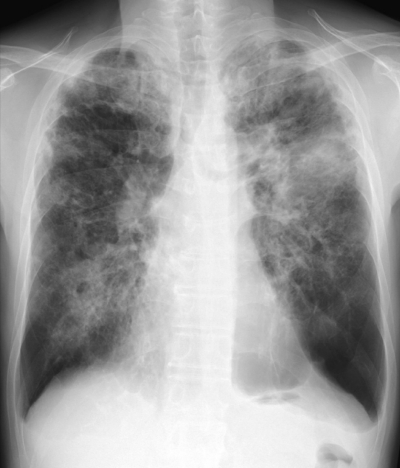

45 歳の男性。喀痰を主訴に来院した。1年前から茶褐色の細長い粘稠な痰をしばしば喀出するようになった。小児期から喘息で治療中である。胸部エックス線写真の正面像と側面像及び肺野条件の胸部 CTを別に示す。